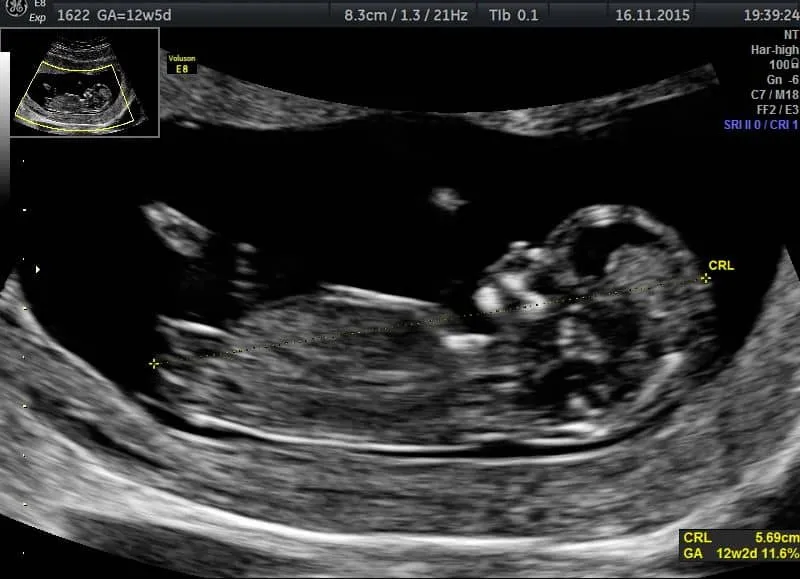

Standardy opieki okołoporodowej w Polsce, czyli rekomendacje PTGiP, jasno wyznaczają termin między 11. a 14. tygodniem ciąży (dokładnie 11+0 a 13+6 tygodnia) jako kluczowy dla pierwszego obowiązkowego badania USG. To badanie ma ogromne znaczenie diagnostyczne i pozwala na kompleksową ocenę rozwoju maluszka.

- Precyzyjne określenie wieku ciążowego na podstawie pomiaru CRL (długości ciemieniowo-siedzeniowej).

Długość ciemieniowo-siedzeniowa (CRL) to pomiar od czubka głowy do pośladków płodu. Na jej podstawie ustalamy termin porodu z największą precyzją. Jest to kluczowe dla dalszego prowadzenia ciąży, monitorowania wzrostu płodu i planowania ewentualnych interwencji.

Pomiar przezierności karkowej (NT) oraz ocena kości nosowej (NB) to bardzo ważne markery, które pomagają nam ocenić ryzyko wystąpienia wad genetycznych, głównie zespołu Downa. Pamiętajcie, że są one elementem tzw. testu PAPP-A, który łączy wynik USG z badaniem krwi, dając nam kompleksową ocenę ryzyka.

Na tym etapie możemy już wykryć niektóre poważne nieprawidłowości w anatomii płodu. Oczywiście, nie wszystkie wady są widoczne tak wcześnie, ale USG I trymestru daje nam cenne informacje i w razie potrzeby pozwala na zaplanowanie dalszej, pogłębionej diagnostyki.